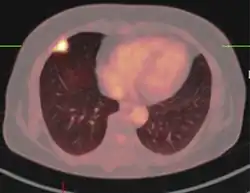

-

PET-CT of a tuberculoma.